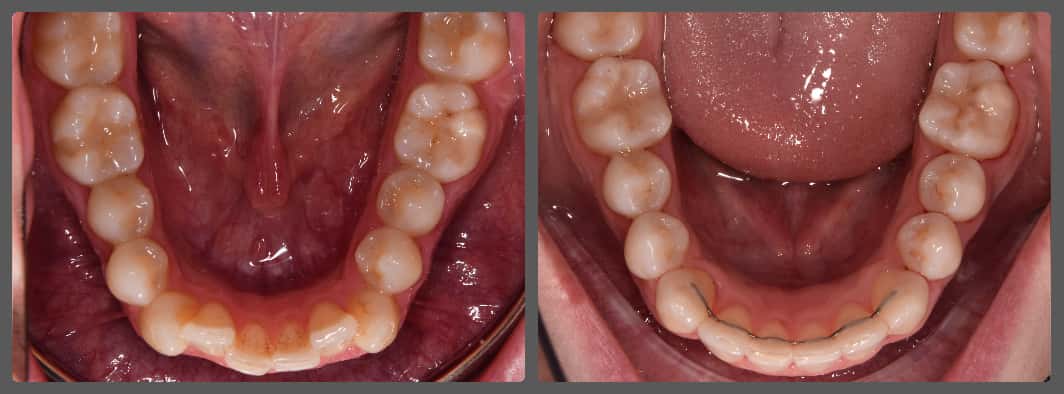

Balázs súlyos alsó torlódása miatt keresett fel magánrendelésemen. A diagnosztikus vizsgálatok során előbbin túl alsó-felső fogívszűkületet, valamint nyitott harapási hajlamot állapítottam meg. Kezelését Pitts21 alsó-felső rögzített fogszabályozó készülékkel kezdtük meg. A nyitott harapási hajlamot a hátsó fogakra helyezett harapásemelővel kontrolláltuk. A torlódott fogaknak tolórugóval és interproximális redukcióval teremtettünk helyet, és intermaxilláris gumihúzással tökéletesítettük a harapást. A fogszabályzó kezelés teljes időtartama alatt Balázs 110%-osan együttműködő volt, ezért 21 hónap alatt sikerült kiemelkedő végeredményt elérnünk.